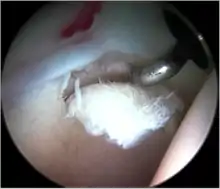

Standard arthroscopic treatment of symptomatic cam FAI involves debridement (resection) or repair of any labral [10] and chondral injuries [11] in the central compartment of the hip, and subsequent reshaping of the head-neck junction of the upper femur (osteochondroplasty) in the peripheral compartment [12][13] using high-speed motorised burrs that are similar in design to a dentist's drill (see fig. 9).